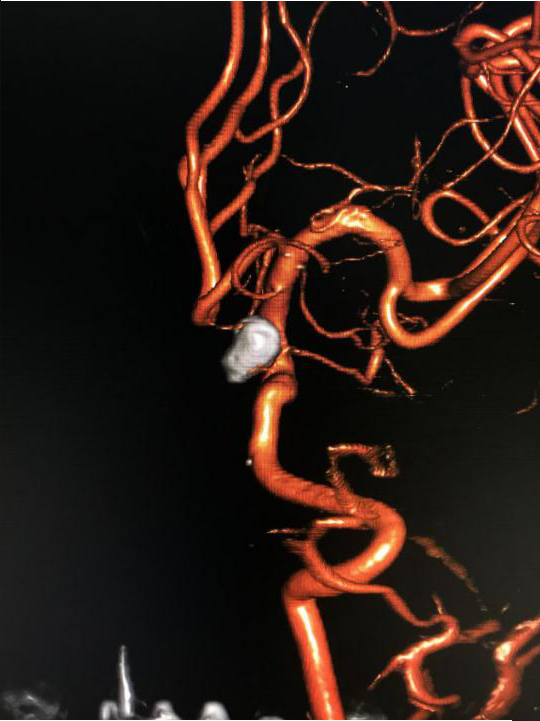

(治疗后三维造影)

入院后第二天,赵师傅被送入杂合手术室,脑血管病组团队医师们登台手术。医生们从赵师傅右股动脉穿刺,将导丝从股动脉、腹主动脉、胸主动脉一路插至颅内载瘤动脉,再运用微导管技术将弹簧圈送到动脉瘤腔内,栓塞瘤腔,在主干血管内置入一枚支架,稳固弹簧圈的同时保留了正常血管的血流。经两个小时手术,赵师傅脑内的动脉瘤被完全填塞封堵。

医生在赵师傅回到病房后严密监测他的心率、血压等各项生命体征,并予以他右下肢制动、脱水、降颅压等对症处理措施。经1周观察治疗,赵师傅恢复良好,顺利出院。